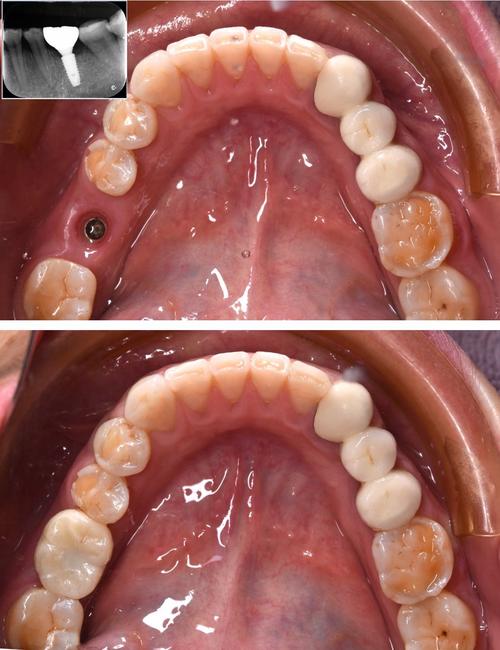

种植牙手术后,牙龈伤口需要通过缝线固定,以促进愈合、防止组织裂开,拆线时间通常根据手术类型、伤口愈合情况而定:一般情况下,简单种植手术(如单颗牙种植,无骨增量等)在术后7-10天拆线;若涉及骨增量、软组织移植等复杂手术,或患者愈合能力较弱(如糖尿病患者、老年人),可能需延长至10-14天,具体时间需医生通过复诊检查伤口愈合程度后确定,过早拆线可能导致伤口裂开,过晚则可能引起缝线刺激或感染。

拆线的核心目的是移除已不再起固定作用的缝线,避免其成为异物刺激牙龈,同时观察伤口最终愈合情况,为后续的修复体戴入(如牙冠)做准备,这一过程虽然看似简单,但患者的疼痛感受往往与操作方式、自身敏感度及术后护理密切相关。